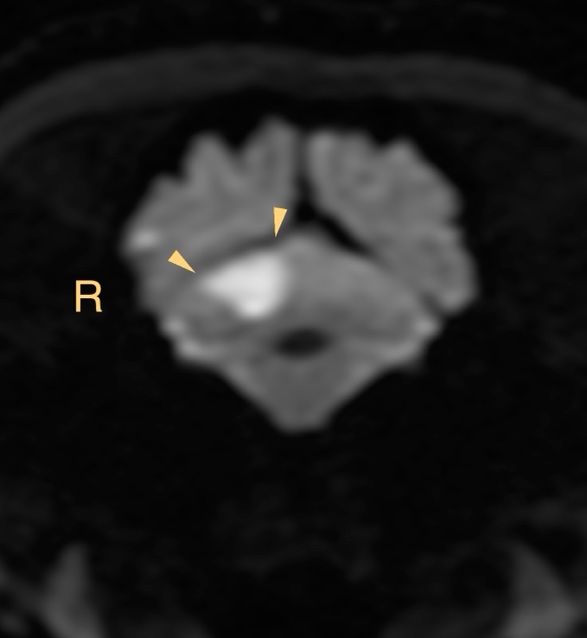

MRI所見

小脳右前小脳動脈領域にT2WI/FLAIR:高信号、DWI:高信号、ADC:一部低信号(部分的な拡散抑制を示唆)

→急性期小脳梗塞を強く疑う所見

この症例もやっぱり小脳中位核を含んでいます、瞳孔不同(右眼散瞳)があったに違いない!!

【MR画像】横断像 拡散強調画像

【MR画像】横断像 拡散強調画像